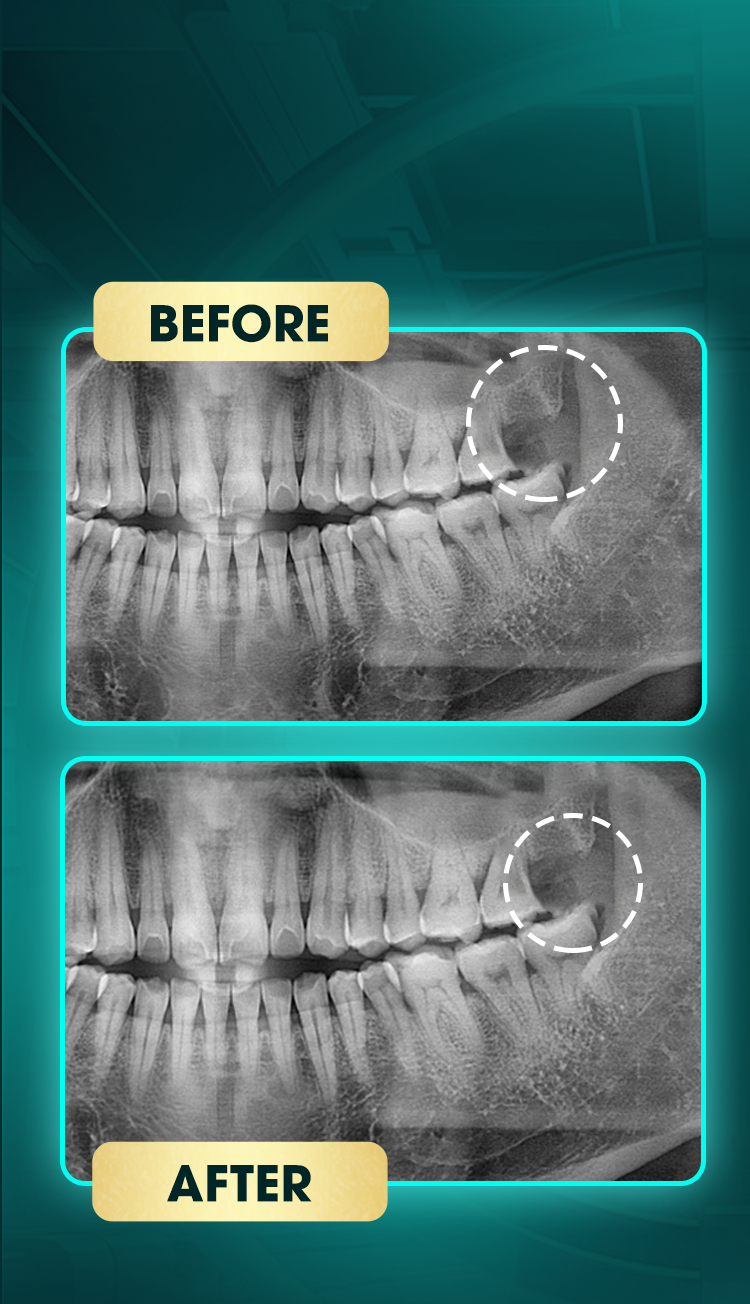

Lư Hoàng Lam

Tiểu phẫu răng khôn

Trước điều trị:

Răng khôn mọc lệch, có dấu hiệu viêm nhẹ vùng nướu quanh răng.

Sau điều trị:

Răng khôn đã được loại bỏ, vùng nhổ lành thương tốt, không còn tình trạng đau hay sưng viêm.

Kết quả: